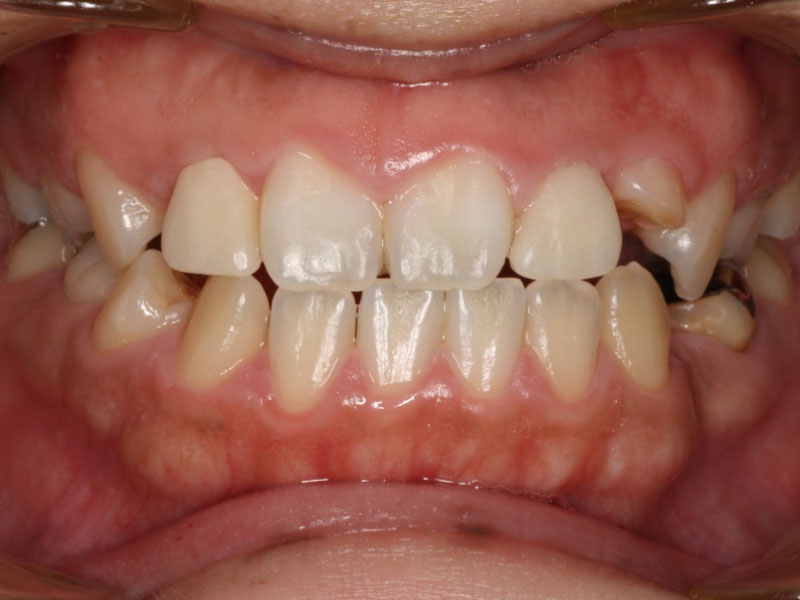

before

経過

after